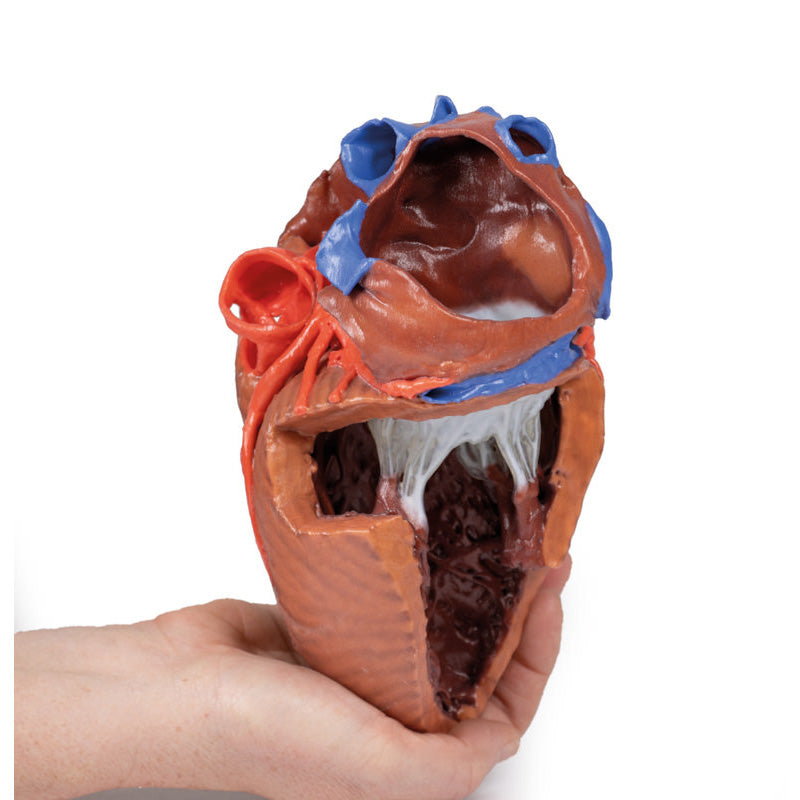

The anterior wall of the right ventricle has also been removed to expose the right atrioventricular valve and its three cusps (anterior, posterior, and septal), including the chordae tendineae connecting them to respective papillary muscles projecting from trabeculae carneae (including a septomarginal trabecula entering the anterior papillary muscle from the interventricular septum). The smooth wall of the conus arteriosus is also exposed leading to the pulmonary semilunar valve (left, right, and anterior cusps) at the base of the pulmonary trunk. Preserved and encircling the right atrioventricular valve is the right coronary artery, ultimately passing to the posterior aspect and the origin of the posterior interventricular artery and atrioventricular nodal artery.

The walls of the opened left ventricle preserve well-developed trabeculae carneae. At the apex of the ventricle the aortic semilunar valve (with left, right, and posterior cusps preserved) can be seen at the base of the sectioned aorta alongside the origin of both coronary arteries. The left coronary artery in this specimen is very short, giving rise almost immediately from its origin to the left anterior descending artery, the diagonal artery, the ramus intermedius, and the circumflex branch. The latter branch passes between the left atrium and ventricle adjacent to the opened coronary sinus leading to the right atrium. The left anterior descending branch penetrates the myocardium in this individual and travels through the tissue, only emerging superficially to become visible again near the apex.

This 3D printed heart has been dissected to display the internal structures of the chambers. At the base of the heart the termination of the superior vena cava is preserved entering the right atrium. Part of the inferior vena cava is also preserved on the inferior aspect of the right atrium; however, most of the vessel lumen and much of the anterior wall has been removed to expose the pectinate muscles of the right auricle and the fossa ovalis (which is nearly translucent in the 3D print).The anterior wall of the right ventricle has also been removed to expose the right atrioventricular valve and its three cusps (anterior, posterior, and septal), including the chordae tendineae connecting them to respective papillary muscles projecting from trabeculae carneae (including a septomarginal trabecula entering the anterior papillary muscle from the interventricular septum). The smooth wall of the conus arteriosus is also exposed leading to the pulmonary semilunar valve (left, right, and anterior cusps) at the base of the pulmonary trunk. Preserved and encircling the right atrioventricular valve is the right coronary artery, ultimately passing to the posterior aspect and the origin of the posterior interventricular artery and atrioventricular nodal artery.

The walls of the opened left ventricle preserve well-developed trabeculae carneae. At the apex of the ventricle the aortic semilunar valve (with left, right, and posterior cusps preserved) can be seen at the base of the sectioned aorta alongside the origin of both coronary arteries. The left coronary artery in this specimen is very short, giving rise almost immediately from its origin to the left anterior descending artery, the diagonal artery, the ramus intermedius, and the circumflex branch. The latter branch passes between the left atrium and ventricle adjacent to the opened coronary sinus leading to the right atrium. The left anterior descending branch penetrates the myocardium in this individual and travels through the tissue, only emerging superficially to become visible again near the apex.